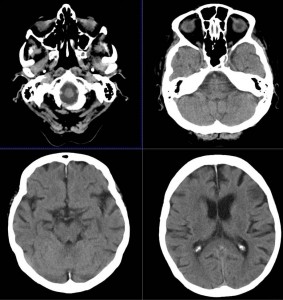

CT検査とはレントゲン(X線)を利用し身体の写真を撮影する検査です。

マルチスライスCT撮影装置

当院では、ドイツ・シーメンス社製マルチスライスCTを導入いたしました。

この装置は高速で回転し、短い時間で検査が可能な最先端マルチスライスCTで、従来の装置と比較して息を止める時間が短縮されます。また細かい情報を得ることができ、脳や腹部の血管や骨などの3D画像(立体再構成画像)を高精細に描出可能です。さらに、X線の被ばくも従来のCT装置に比べ低減されています。

頭だけではなく、全身のCTを撮ることが出来ます。